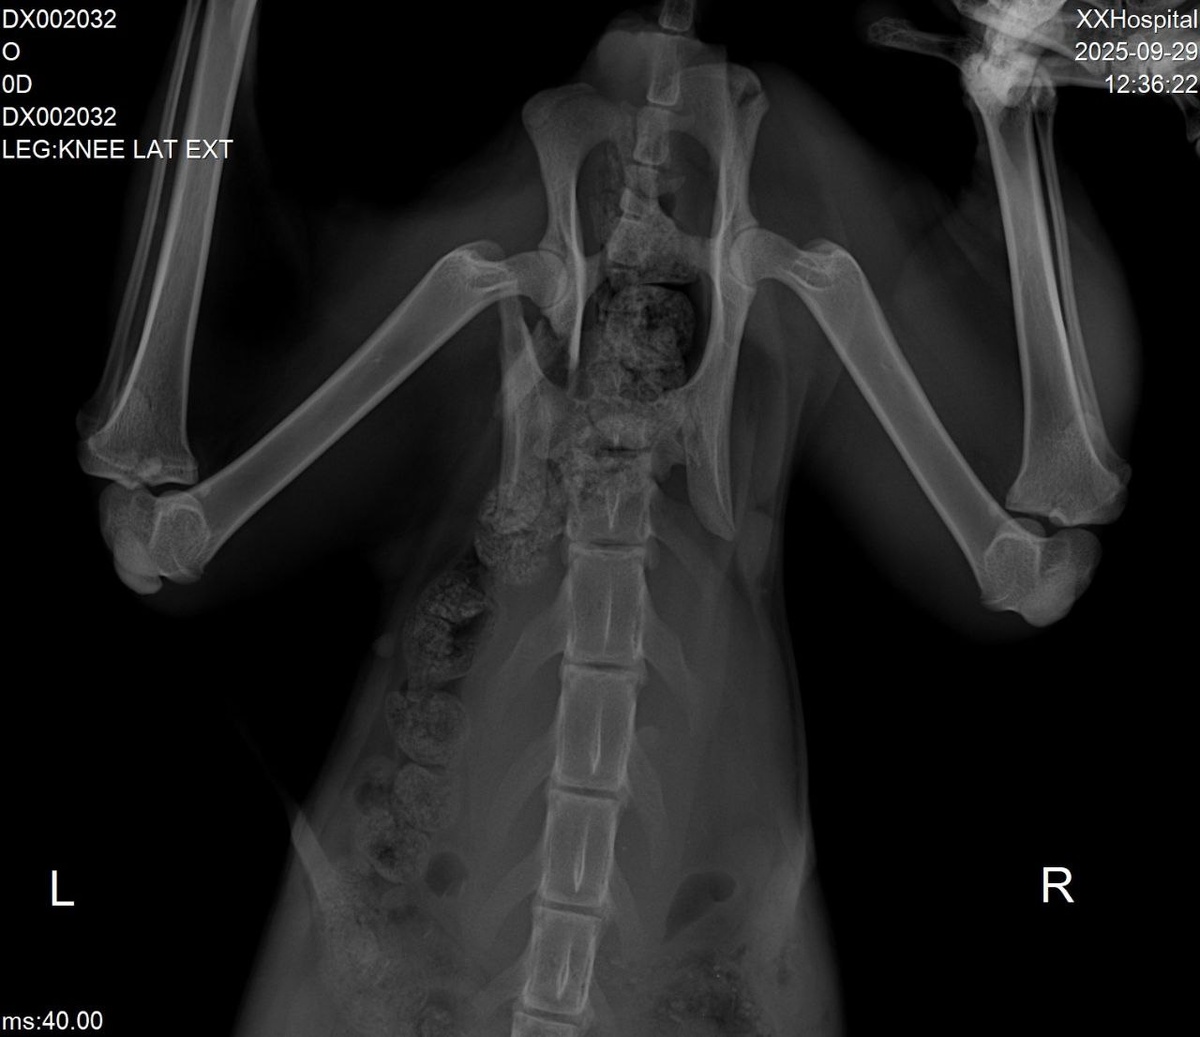

🆘🆘🆘У кошечки сломан таз, СРОЧНО нужна операция,времени очень мало, каждый пройденный день может усложнить операцию, стоимость в районе от 25-30 тыс, плюс реабилитация😢Кошечка практически не ходит, в основном лежит😭помогите , пожалуйста, собрать на операцию, каждые 50-100 руб. будут огромной помощью🙏 До этого было собрано 4300-1500(рентген)-270(от паразитов)-1000(зоотакси)=остаток 1530 руб. Помощь можно оказать по номеру: +7 961 055-29-86 Т-банк Елена К. С пометкой БЛАГОТВОРИТЕЛЬНОСТЬ КОШЕЧКЕ🙏 Отчет гарантирую‼️

До этого было собрано 4300-1500(рентген)-270(от паразитов)-1000(зоотакси)=остаток 1530 руб.